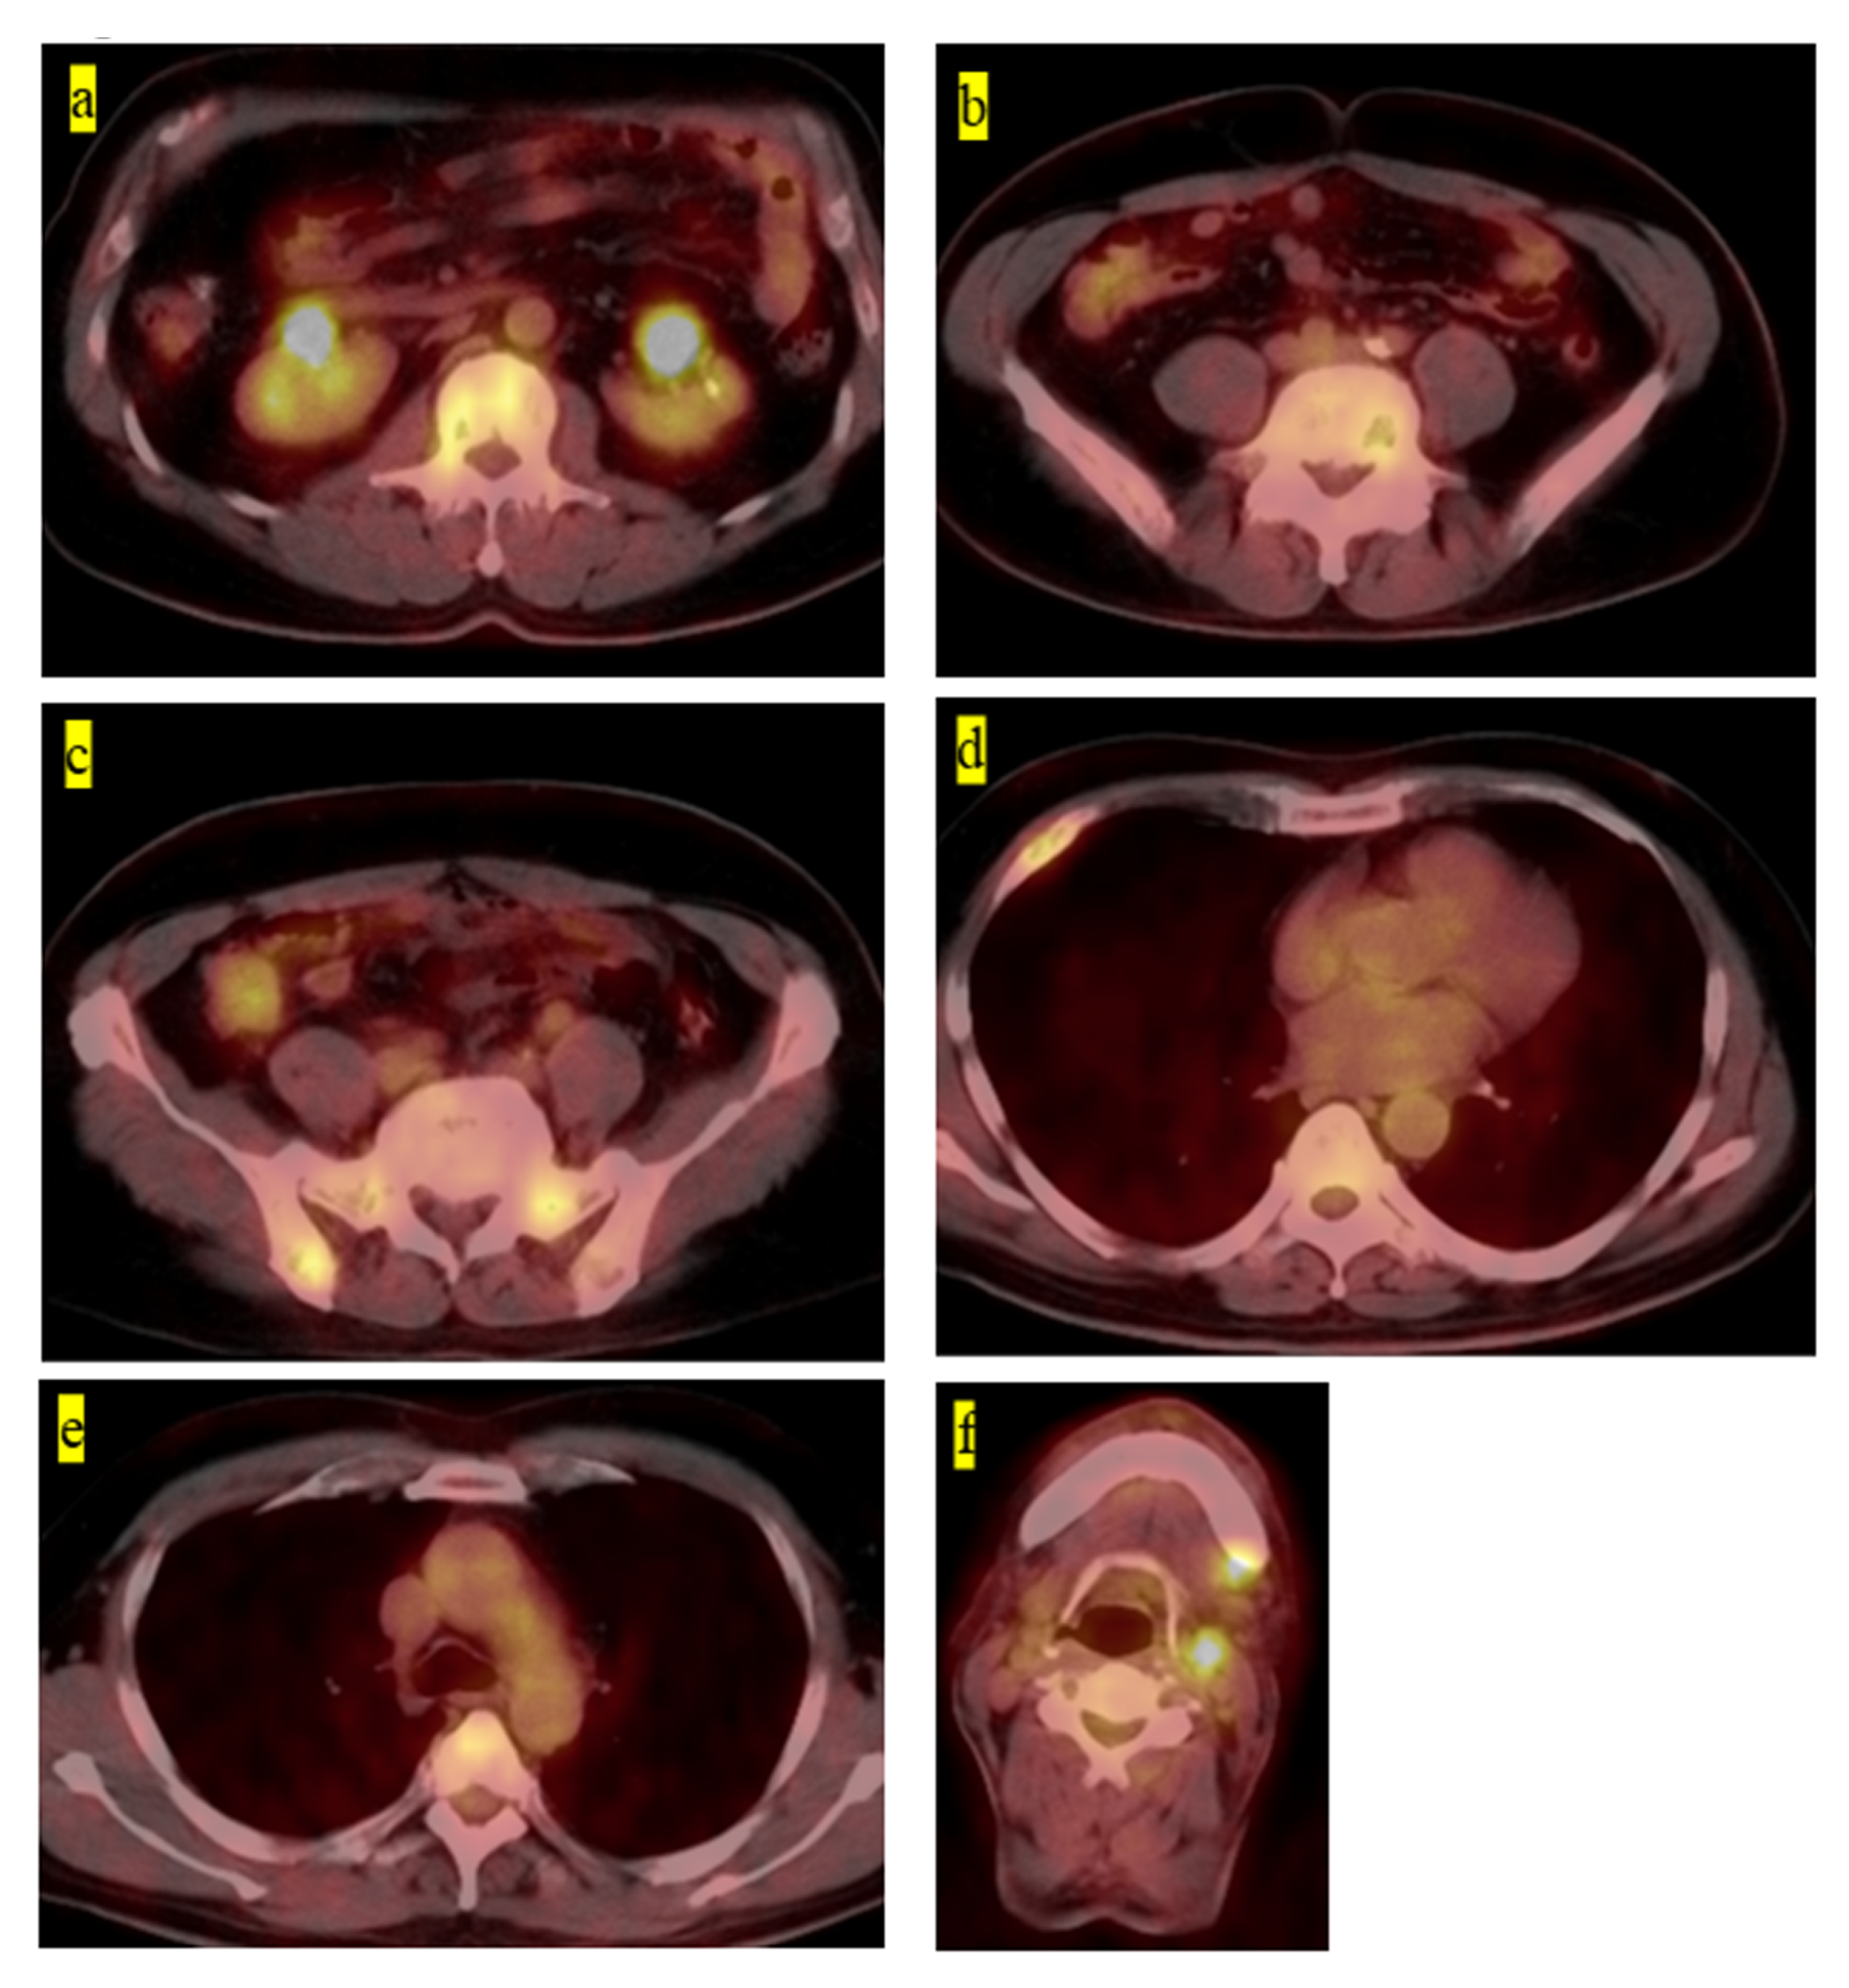

| 2 | 60 | M | Second, third, fourth, fifth lumbar, Th10, rt fourth rib, sacrum, pelvic | Radiography, MRI, PET-CT | Without symptoms | Hepatitis B | Fifth lumbar | Chemotherapy (6-mercaptopurine 110 mg, MTX 2.5 mg, PSL 5 mg) | CDF | 63 |